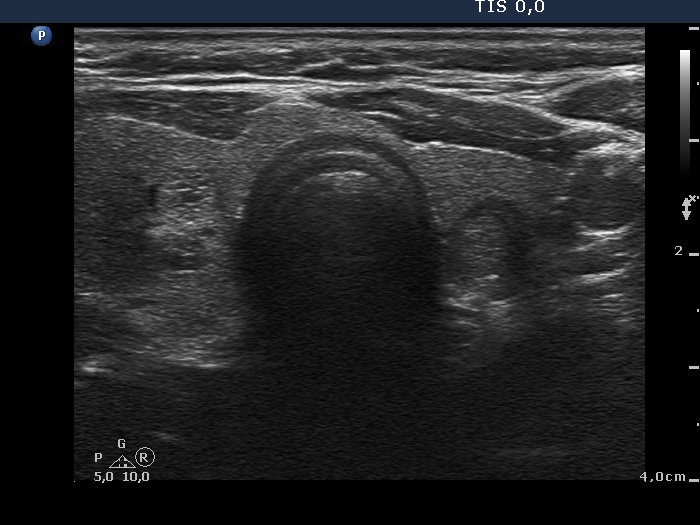

The composition of the nodule - case 1473 (ultrasonographic picture 6)

Horizontal view of the lower part of the thyroid. There are two other lesions, a hyperechogenic one in the right and a hypoechogenic one in the left lobe.